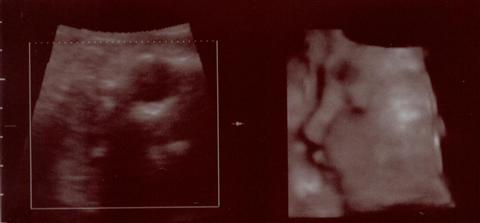

Echo003.jpg